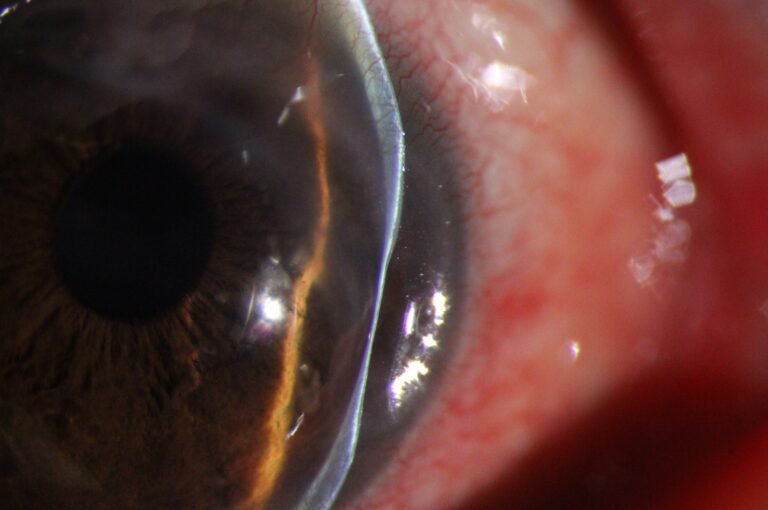

Precision Optics

Premium Optical System

High-resolution visualization across a wide range of magnifications. Multi-coated optics deliver distortion-free anterior segment imaging for confident clinical assessment.

- 5 Step Magnification: 6×, 10×, 16×, 25×, 40×